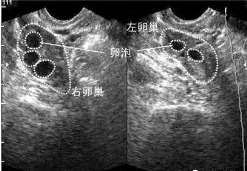

乌鲁木齐为什么专家不建议试管婴儿的_正规辅助生殖中心 高龄女性备孕期间成功率多少,首先是看女性的卵泡发育情况, […]